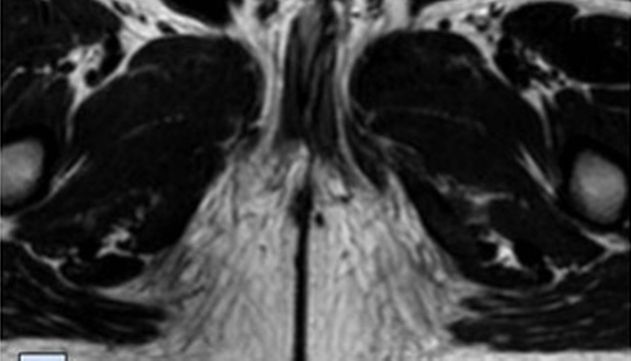

Ressonância magnética dos órgãos pélvicos, incluindo estruturas penianas, de menino que nasceu com difalia

O caso do menino analisado no estudo, descrito como "um grande desafio cirúrgico", foi classificado como "difalia completa verdadeira", pois o exame físico inicial identificou dois pênis completamente desenvolvidos e estruturalmente normais, com fluxo de urina em ambas uretras.